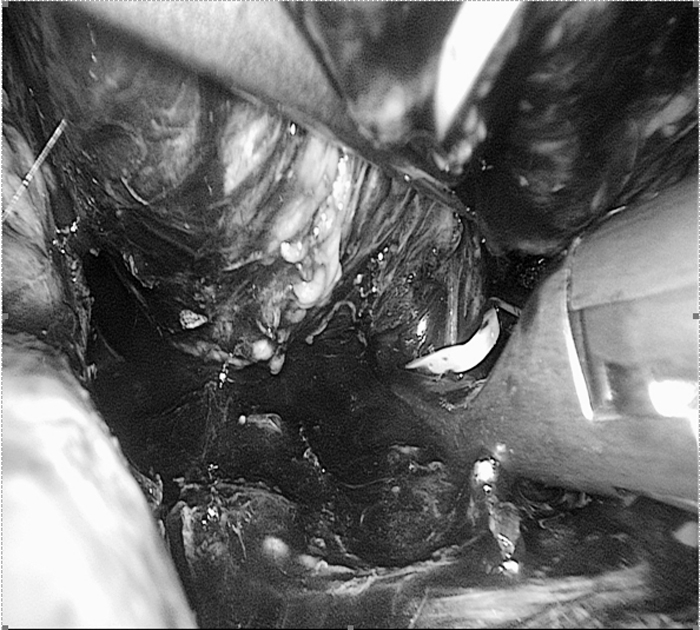

手術(shù)中影像(圖片已做處理)

??? 麻醉科余功敏主任醫(yī)師已經(jīng)和萬醫(yī)生配合完成了好幾臺嗜鉻細(xì)胞瘤的手術(shù)。手術(shù)當(dāng)日,余功敏在完成了深靜脈穿刺、動脈穿刺和氣管插管后,又在一旁準(zhǔn)備了自體血回輸設(shè)備,說:“你放心開始手術(shù)吧!”術(shù)中雖然經(jīng)歷了血壓飆升和血壓下降,但余功敏鎮(zhèn)定自若,降壓藥和升壓藥輪流上陣。經(jīng)過嚴(yán)密的麻醉監(jiān)護(hù)、精確的術(shù)中操作,一個(gè)小時(shí)后在腹腔鏡下有驚無險(xiǎn)地順利切除腫瘤。手術(shù)順利,老太太術(shù)后恢復(fù)快,第五天就出院。